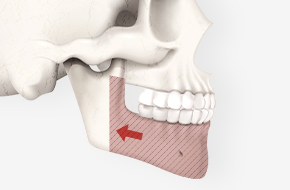

작은 어금니를 발치한 뒤, 위아래 잇몸뼈를 삭제합니다.

제거된 치아와 잇몸뼈만큼 턱뼈를 뒤쪽으로 이동시켜 과도한 돌출 증상을 해소합니다.

돌출입 수술은 단순히 돌출된 입을 밀어 넣는 것이 아니라,

코 끝부터 인중, 입술을 거쳐 턱 끝까지

자연스러운 라인을 완성하는 것이 핵심입니다.

코 끝과 인중, 입술과 턱 끝, 그리고 치아 각도까지 고려하여

입체적인 얼굴 옆 라인을 완성합니다.